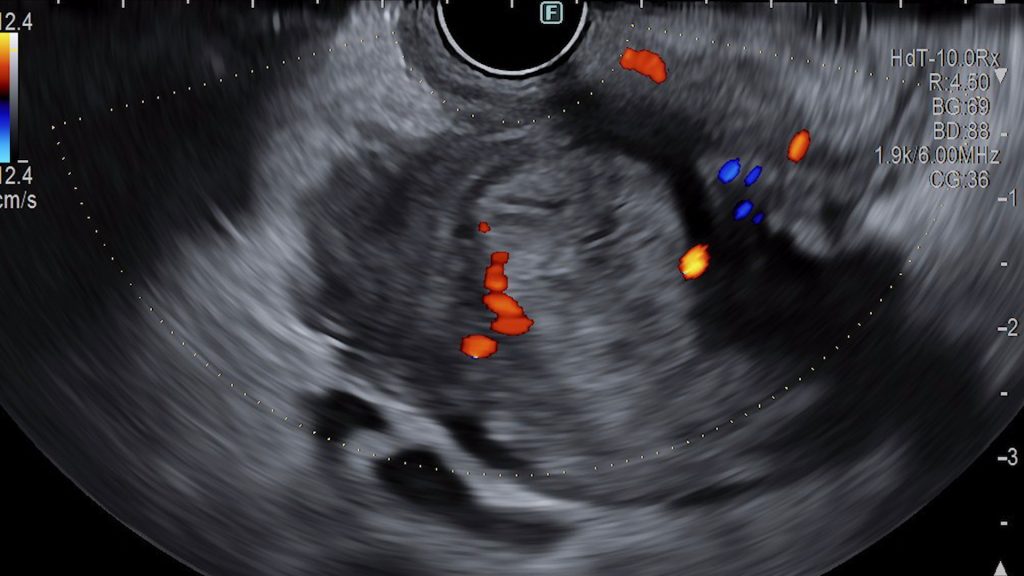

Endoscopic Ultrasound Management of Duodenal Stenosis in Groove Pancreatitis

A 75-year-old patient, smoker, chronic alcohol consumer, with dyslipidemia and peripheral arterial disease with a femoral stent, presenting as an emergency for persistent emetic syndrome that began approximately 6 months earlier, with worsening over the past 2 months, accompanied by inability to eat and abdominal pain.

Ecoendoscopy